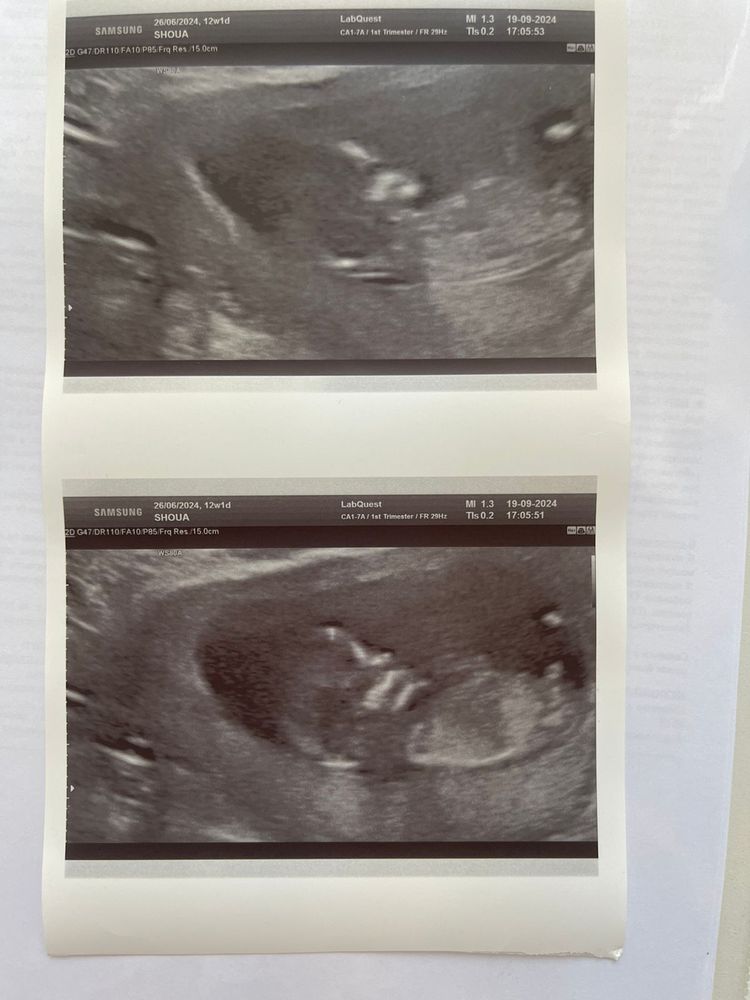

Узи на 12 неделе

90% что будет мальчик 🥰

ИзображениеПохоже на парня

Это мальчик))

Девочка

Очень четкий мальчик) Но понятно, что если бы по бугоркам на 100% можно было сказать пол, то все узисты проще на первом узи бы пол говорили, чем потом ловить ножки малыша в положении, которое покажет пол.

Возможно мальчик))

Похож на мальчика